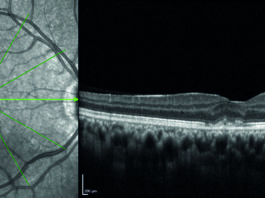

È diffusamente riconosciuto che il glaucoma è una neuropatia cronica e progressiva del nervo ottico e che...